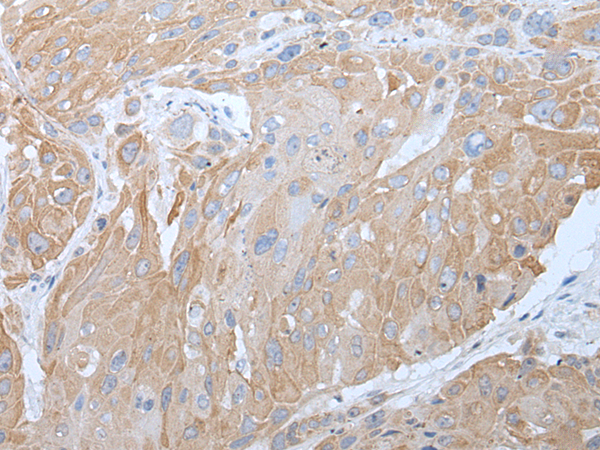

分类: 科研抗体货号: P12777别名: LRPB7应用: IHC反应种属: Human